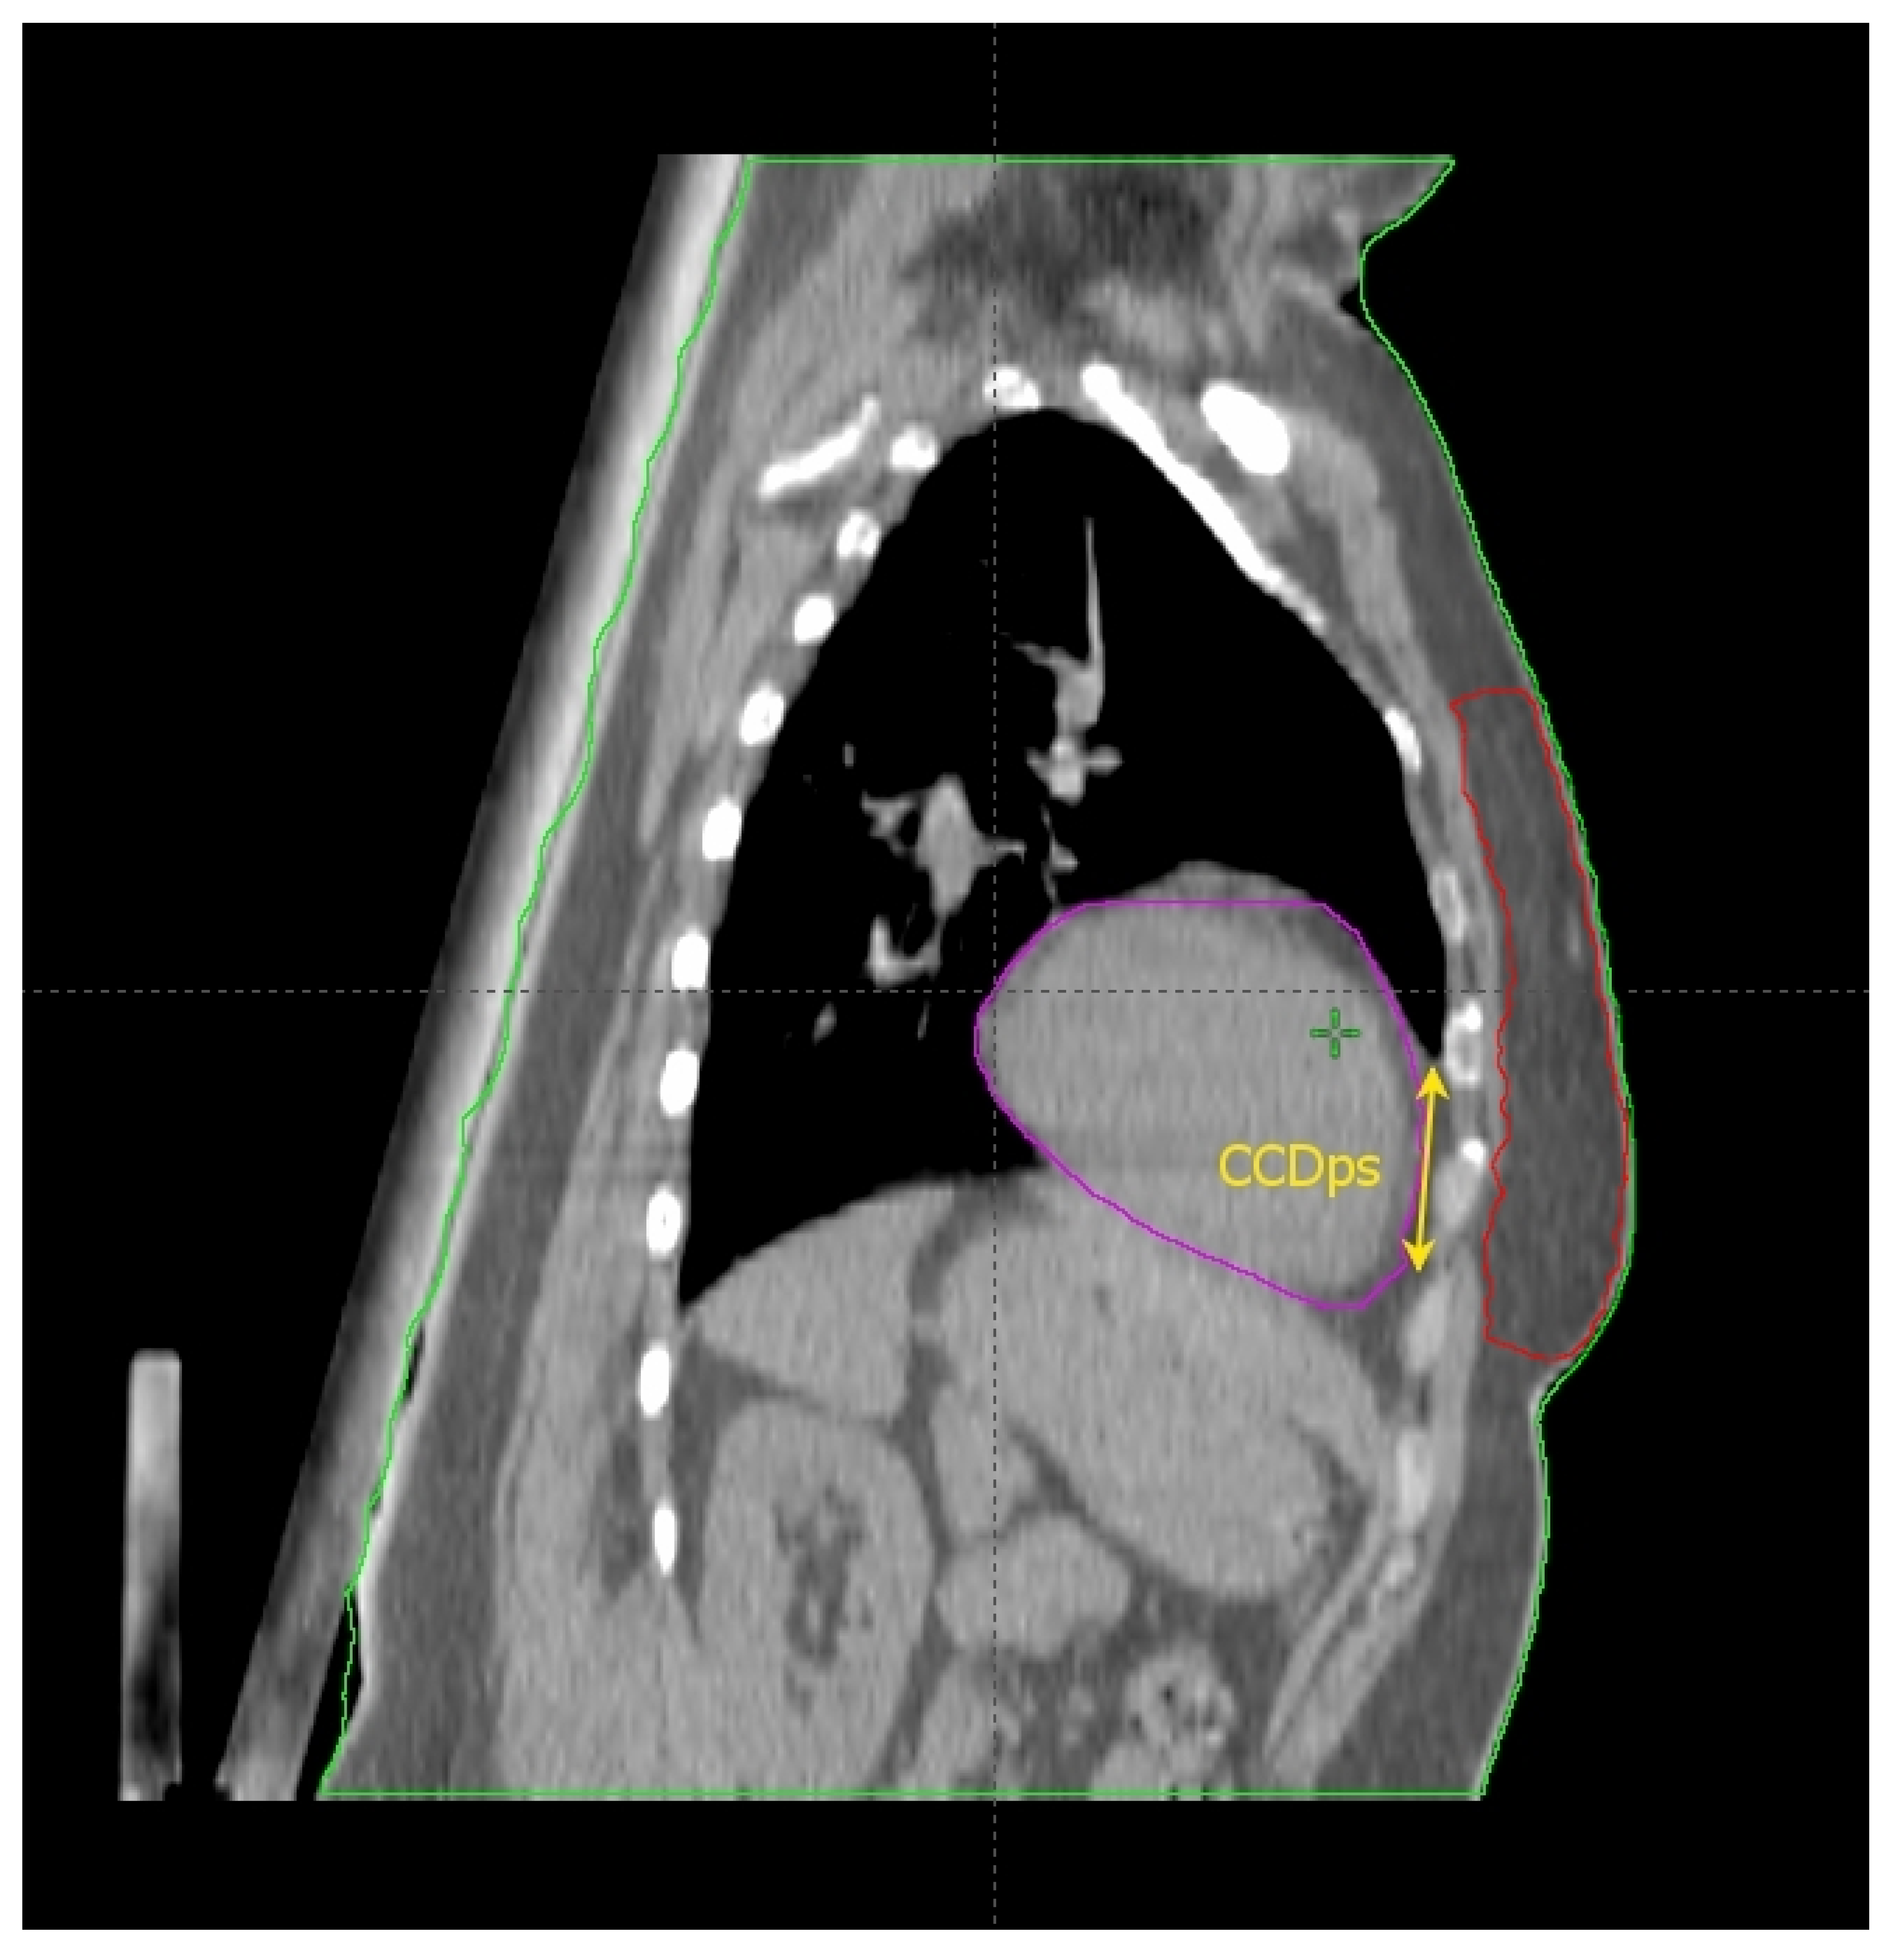

2.2. The Cardiac Contact Distance in the Axial (CCDax) and Parasagittal (CCDps) Planes and the Lateral Heart-to-Chest Distance (HCD)